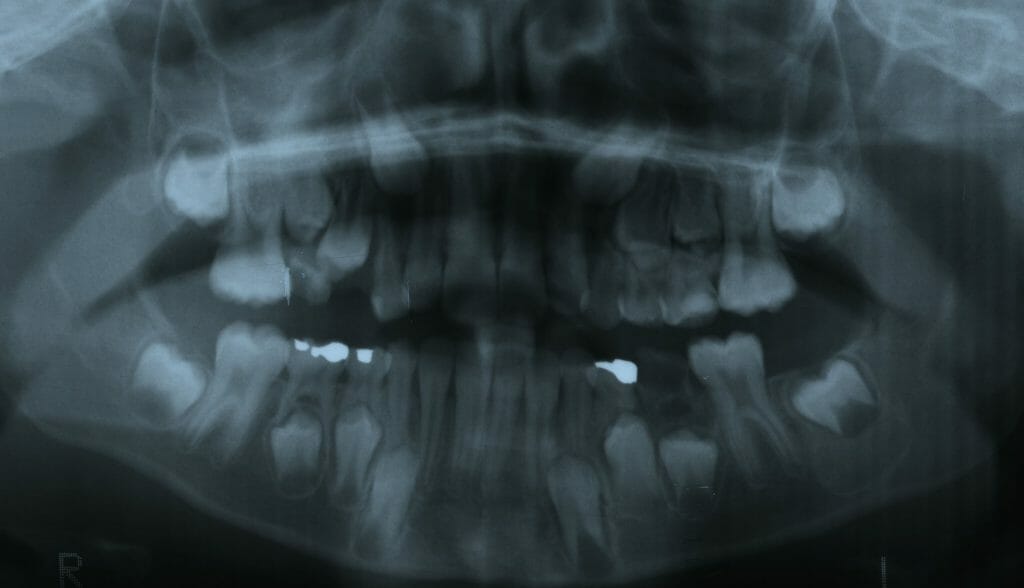

Dès l’âge de 7 à 8 ans, un enfant qui présente un des signes suivants peut être vu en consultation orthodontique.

Tout enfant présentant un des signes suivants peut être vu en consultation orthodontique afin d’établir un diagnostic et proposer un traitement interceptif de phase I le cas échéant.

Il est toujours souhaitable que le patient présente les 8 incisives et les premières molaires permanentes afin de maximiser l’intervention thérapeutique à cet âge.